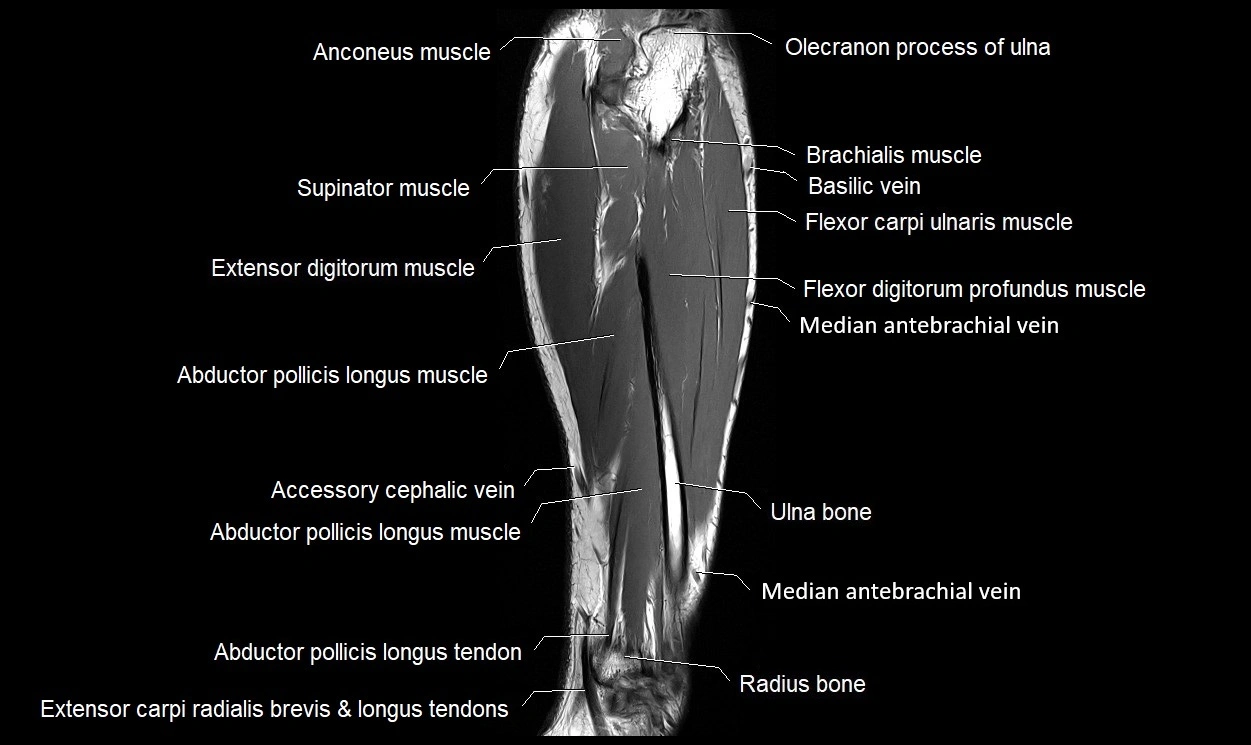

MRI images

image